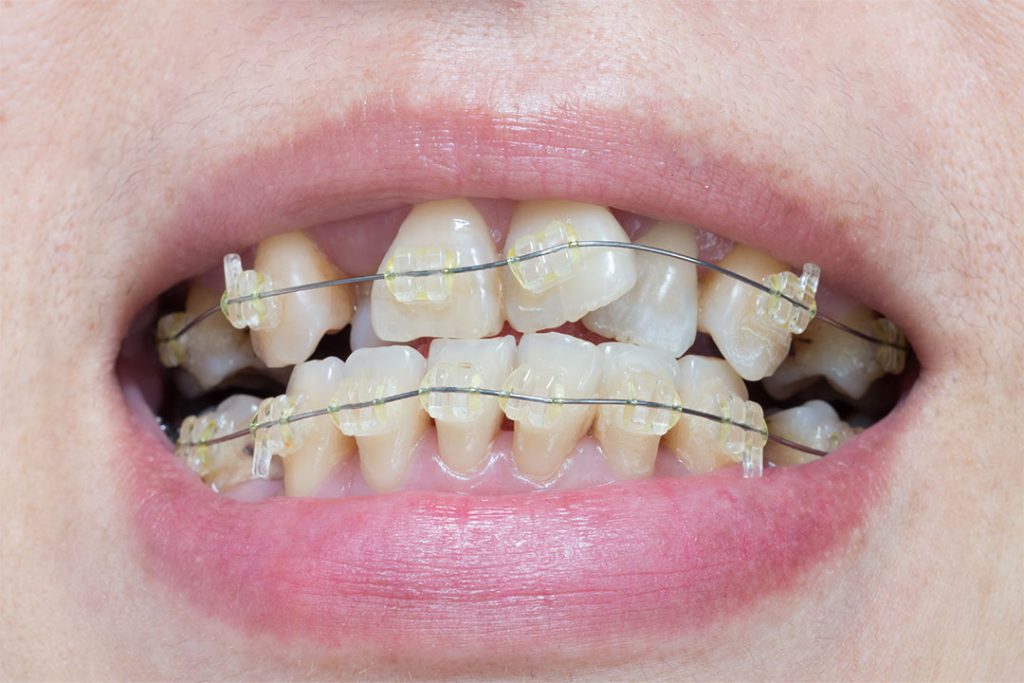

Kieferorthopädische Maßnahmen bei verlagerten Zähnen als Alternative

Eine Freilegung und Anschlingung (Befestigung mit einer (Teil-)Zahnspange) der verlagerten Zähne oder des verlagerten Zahns kann notwendig werden, wenn diese allein den Durchbruch in die Mundhöhle nicht schaffen und im Kiefer bleiben. In Zusammenarbeit mit unseren Bayerwaldzahn-Kieferorthopäden/-Kieferorthopädinnen erarbeiten wir in solchen Fällen einen Behandlungsplan. Bei der Durchführung der kieferorthopädische Maßnahme wird der Zahn freigelegt und mit einem sogenannten „Bracket“ inklusive eines Kettchens direkt auf die Krone aufgeklebt. Im Rahmen der weiteren Behandlung wird der/die Kieferorthopäden/Kieferorthopädinnen den betroffenen Zahn oder die betroffenen Zähne aus seiner verlagerten Position heraus in die Zahnreihe bewegen. Eine Erfolgsgarantie kann hier jedoch nicht gegeben werden, sodass der verlagerte Zahn anschließend vielleicht doch chirurgisch entfernt werden muss. Jedoch ermöglicht dieser Versuch doch eine Chance für den Erhalt vieler Zähne, die sonst entfernt werden müssten und somit eine Lücke hinterlassen, die wiederum mit einem festen oder herausnehmbaren Zahnersatz geschlossen werden müsste.

Schiefe Zähne mit Zahnspange